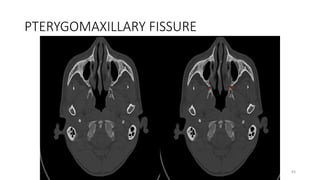

PTERYGOMAXILLARY FISSURE

PTERYGO MAXILLARY FISSURE